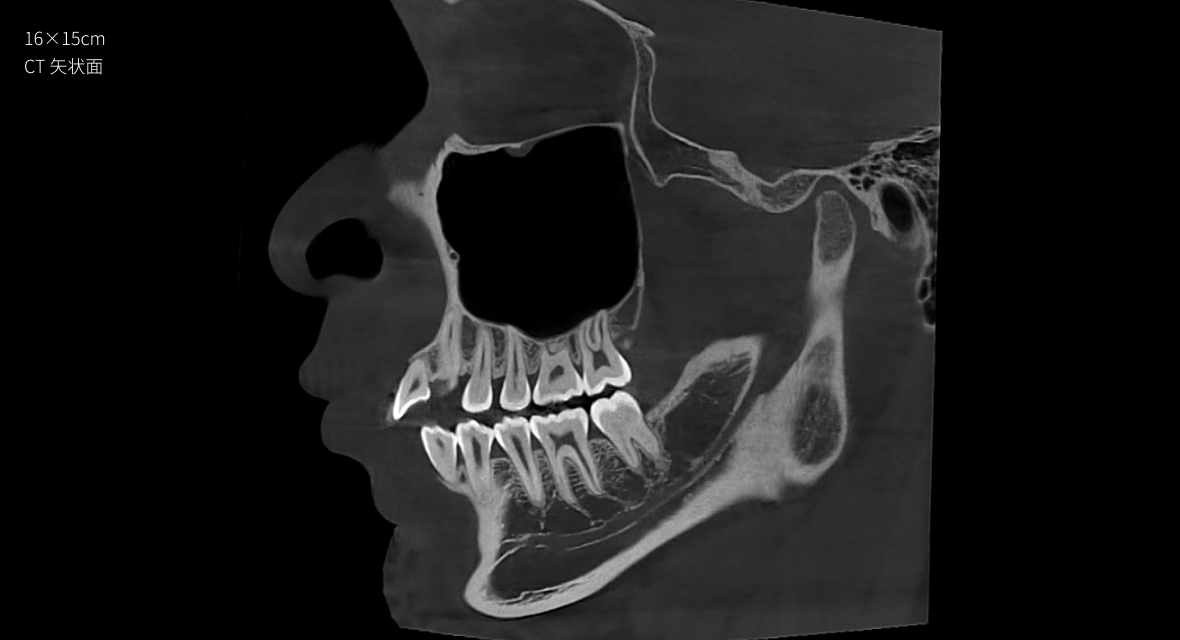

• CT

CT

16×15cm

非拼接大視野

28lp/cm

高精準

Physics-driven系列偽影校正算法

實現高清精準成像

物理驅動

偽影校正算法